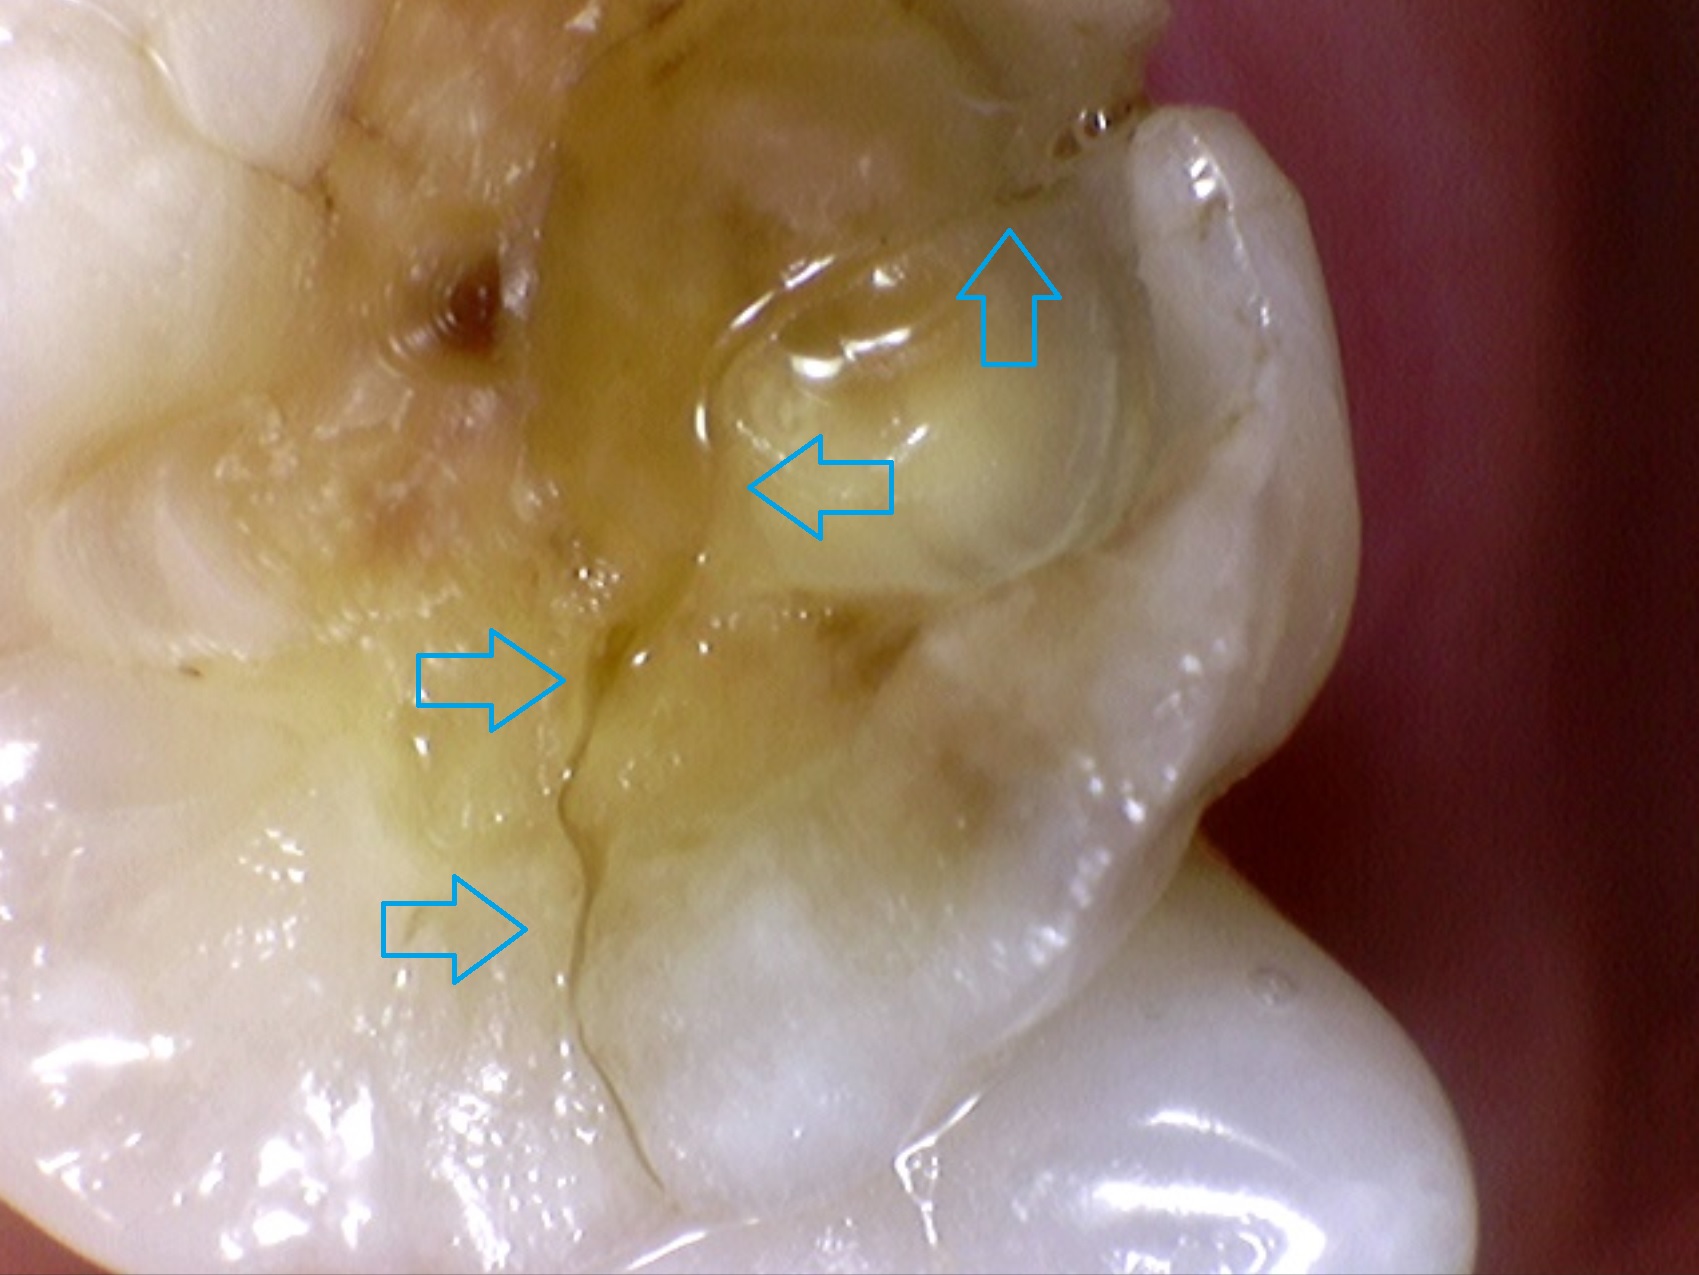

위 환자분은 파란색 화살표로 보이듯이

명확하게 파절선(fracture line)이 보입니다.

하지만 위에 언급해 드린 대로, 환자분은 통증이 없다고 하셨습니다. 그래서 제가 처음부터 파절을 의심하지 못했던 것이었습니다. 하지만 너무나 명확하게 파절선(fracture line)이 보이므로 환자분께 사진을 보여드리며 충분한 설명을 해드렸습니다.

파절편을 제거해 보니 치아-치은(잇몸) 경계 아래쪽까지 깨져 있었으며, 파절편 제거 후 신경치료를 시행하기로 하였습니다.